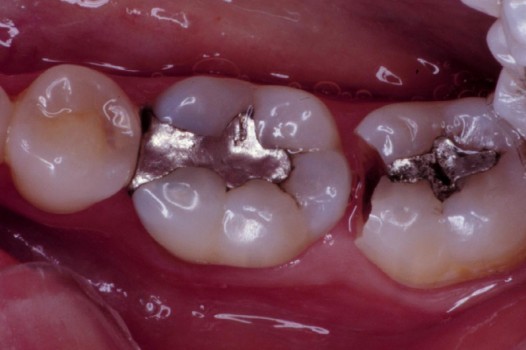

Traditional amalgam (mercury) fillings have been used for over a century, but concerns about health risks, tooth fractures, and long-term decay have led many dentists to adopt modern alternatives. Today, metal-free restorations offer healthier, stronger, and more natural-looking results.

Using advanced resins, ceramics, and state-of-the-art bonding techniques, Dr. Klim can restore teeth with precision, preserving healthy tooth structure while preventing fractures, bacterial invasion, and future toothaches.